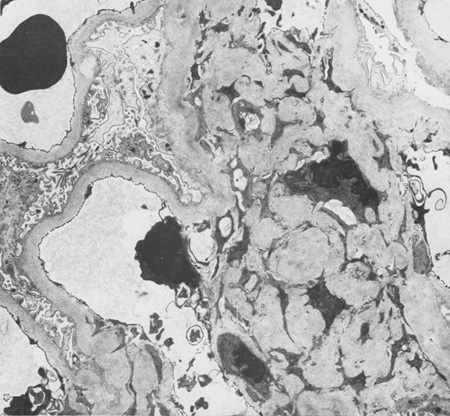

Diabetic kidney disease

Diabetic kidney disease: mesangial expansion due to increased mesangial matrix and decreased degradation of glycosylated collagen

From the collection of Dr Raoul Fresco; used with permission